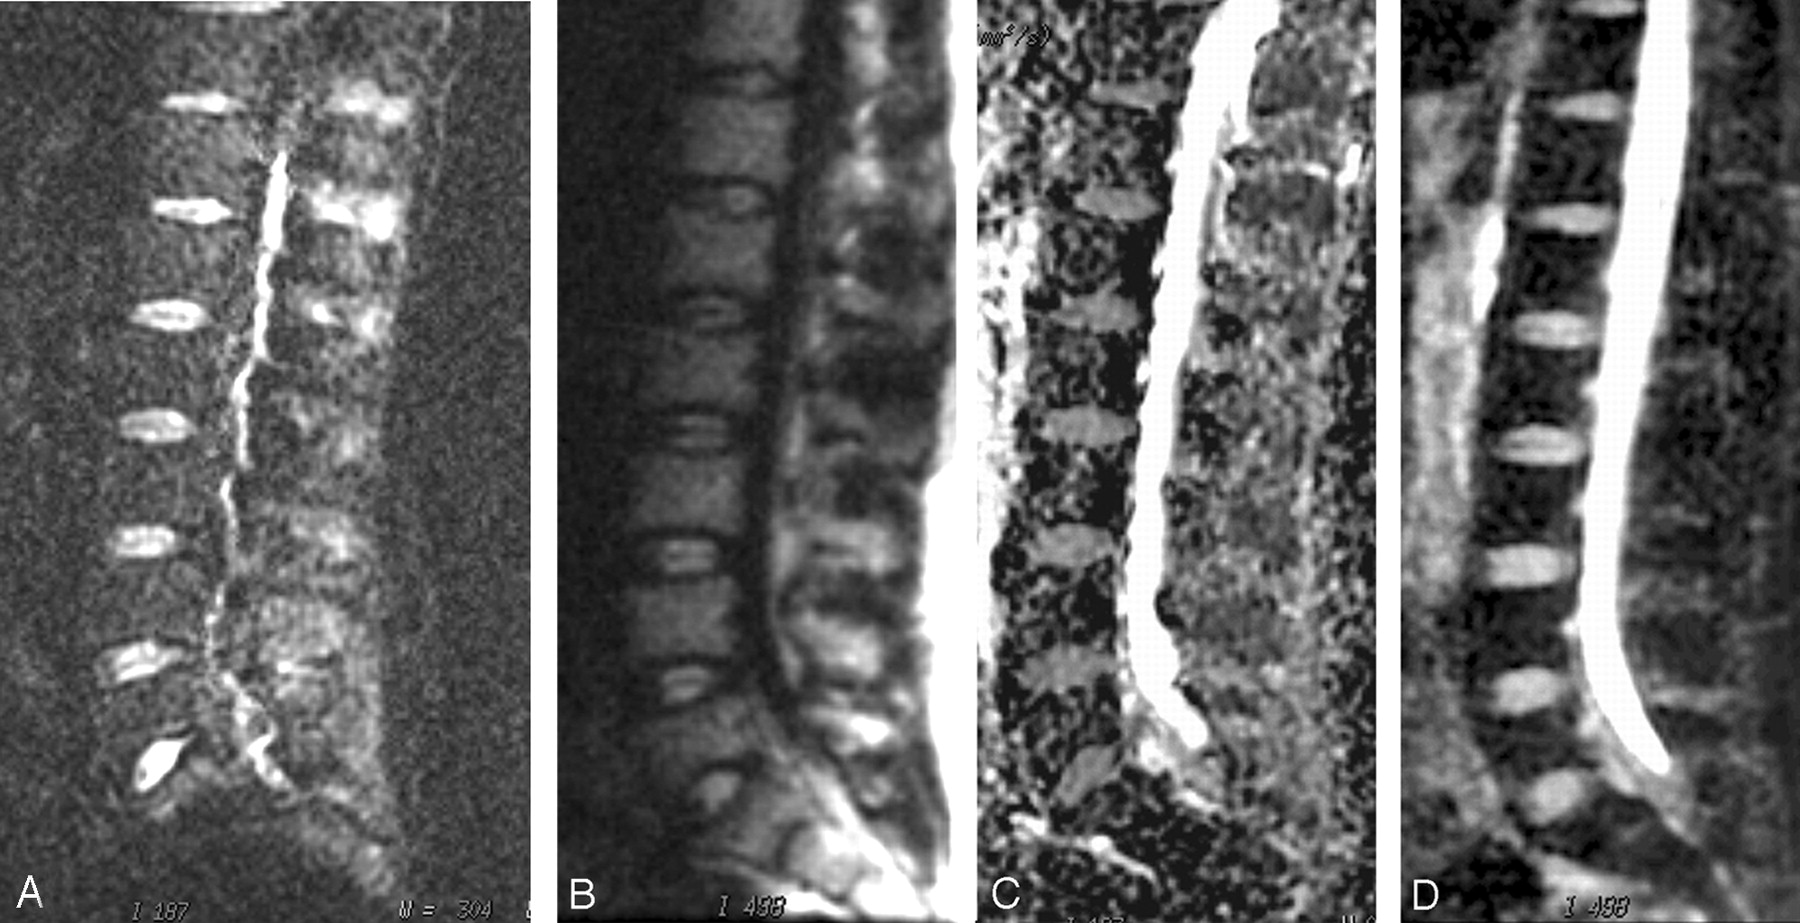

SNR and ADC values obtained from the normal vertebra with 2 different DWI sequences for a b value of 600 mm2/s, and corresponding image quality scores are shown in Table 1. SNR values associated with non-CPMG SS-FSE technique were found to be significantly higher than those measured with the EPI-based DWI technique (P < .01). ADC measurements obtained with EPI-based DWI were found to be significantly higher than the non-CPMG SS-FSE DWI technique. Image quality scores were found to be higher in non-CPMG SS-FSE DWI technique, compared with the EPI-based DWI sequence. Images of a patient with normal MR imaging findings are shown in Fig 1.

Sagittal diffusion-weighted images in a 25-year-old man with normal spine MR imaging findings obtained at the same level with 2 different techniques: EPI DWI at b = 600 mm2/s (A) and non-CPMG SS-FSE DWI at b = 600 mm2/s (B) and corresponding apparent diffusion coefficient (ADC) maps (C and D, respectively). Increased signal intensity, with better background suppression is noted with the non-CPMG SS-FSE technique. ADC values for the L3 vertebra are (mean ± SD) 0.51 ± 0.17 and 0.37 ± 0.14 × 10−3 mm2/s for EPI and non-CPMG SS-FSE DWI, respectively.